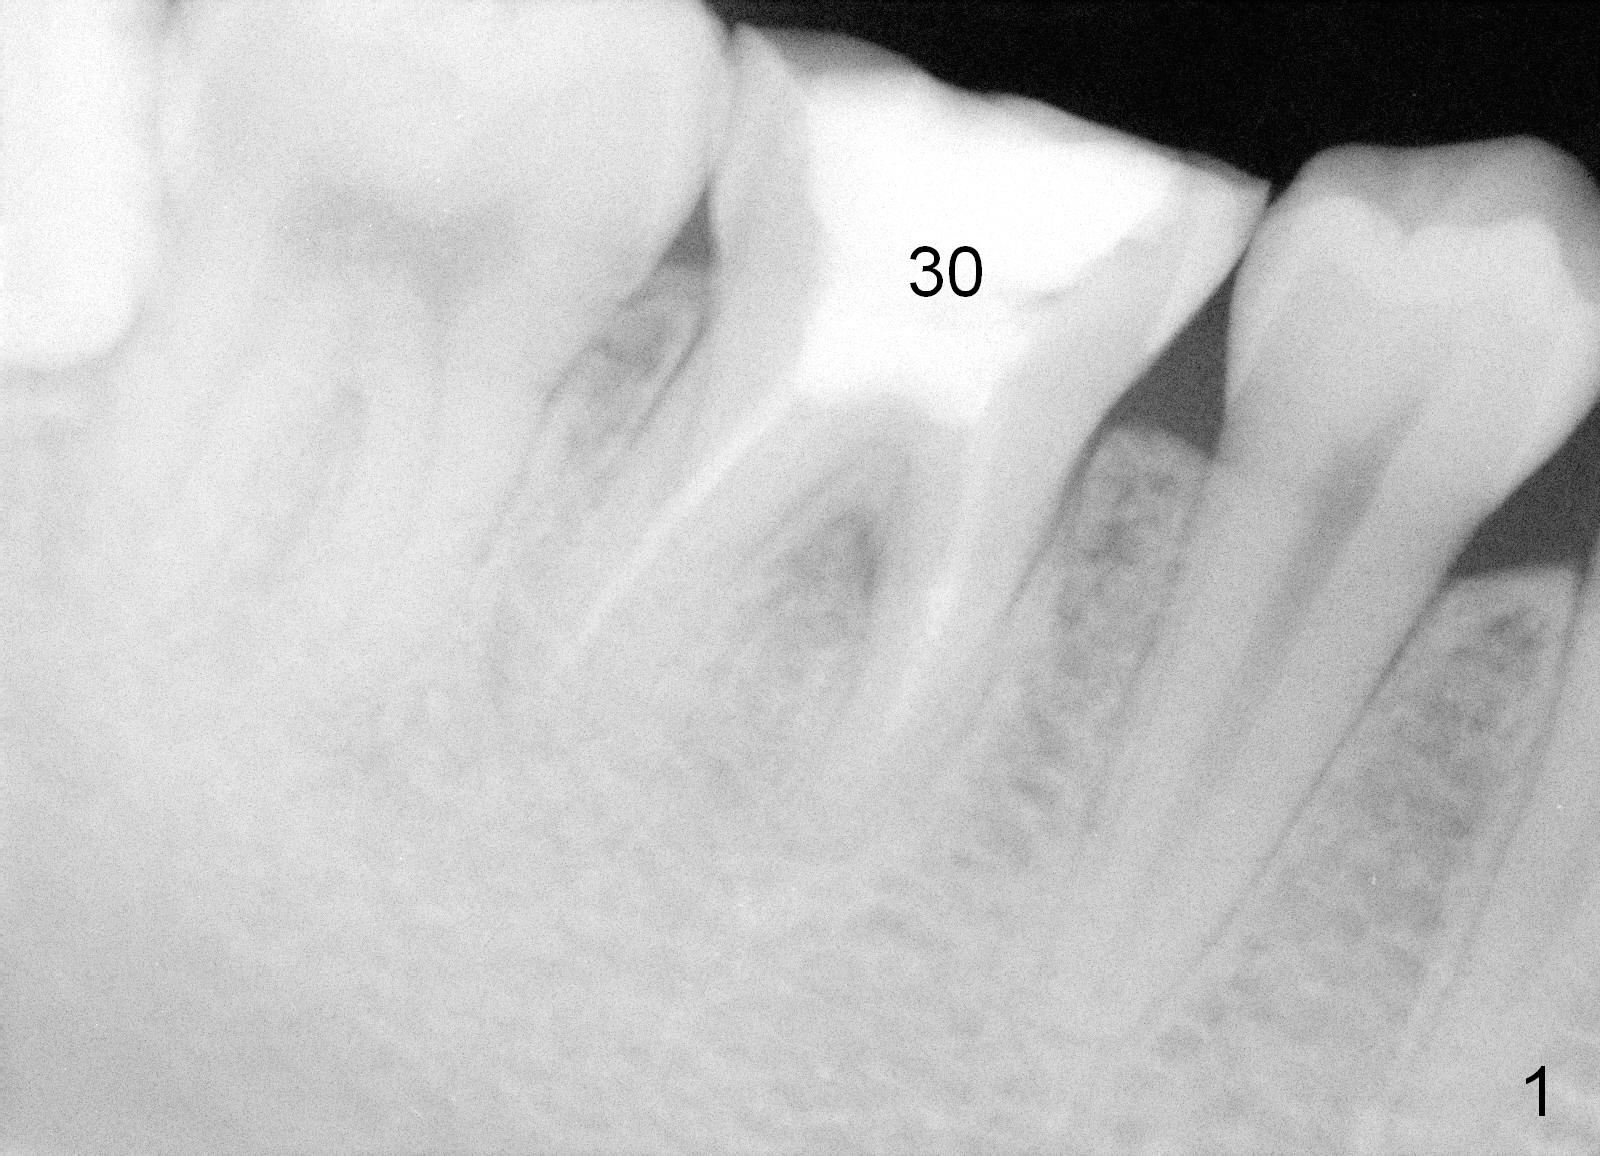

First of all, use a sharp small pilot drill (1.2, 1.5 or 2.0 mm) 3 mm shy of the extended length. For this case, the initial depth will be 14 mm from the gingival margin (Fig.3: red long arrow). If the drill is straight and in the middle of the septum (1st intraop PA), keep drilling for the next 3 mm. If the trajectory is off (Fig.4), withdraw the drill (Fig.5 black long arrow), find a new starting point, change the trajectory and finish osteotomy depth (red long arrow) if the new trajectory is deemed correct. Take more X-ray if necessary.